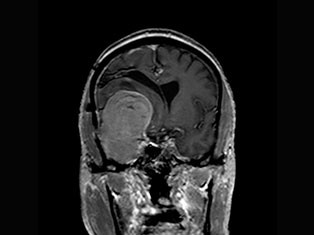

Spinal Tumors

A spinal tumor is a growth that develops within your spinal canal or within the bones of your spine. A spinal cord tumor, also called an intradural tumor, is a spinal tumor that that begins within the spinal cord or the covering.